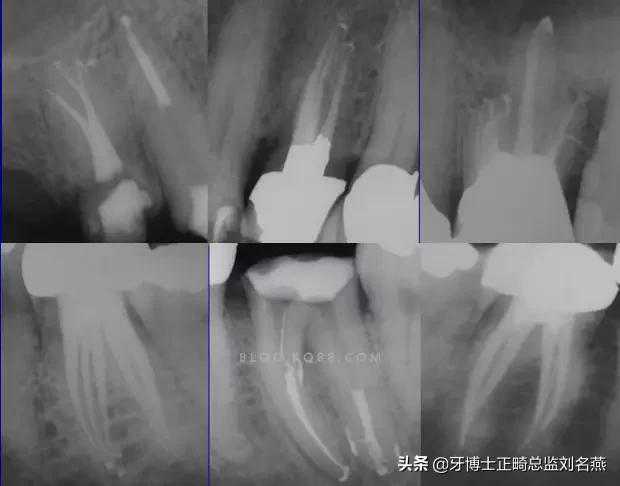

一个牙齿的根管治疗难易程度不单单是根管的弯曲、细小、牙位、是否再治疗决定的,开髓的直线进入和根管口的预先恰当处理可以简化很大的难度,开髓是根管成败的基础。

对于弯曲根管冠部的直线入口就显得尤为重要,冠部良好的直线入口可以避免侧穿、台阶、遗漏根管等问题的发生,冠部直线入口形成的良好情况,取决于医生的理念和合理的器械选择。开髓孔的大小不是由医生和患者的意愿决定的,而是由要治疗牙齿的髓腔大小决定的。

2、相信有更多的根管存在

相信根管的数目比我们想象的多,根管系统的复杂程度比我们想象的见到的要更复杂,我们只有用尽所有努力和办法才可能达到预期目标。

对于上颌第一磨牙的MB2来说过去是偶尔有,现在是偶尔没有,各种文献报道的比例也不一致,在离体牙中几乎还没有见到没有的,临床中也是一样。对于寻找的方法来说,我觉得相信有才是最重要的,首先相信一定有就会想各种办法,找到的几率就会更多。如果有条件在显微镜和超声的配合下效率会更高。